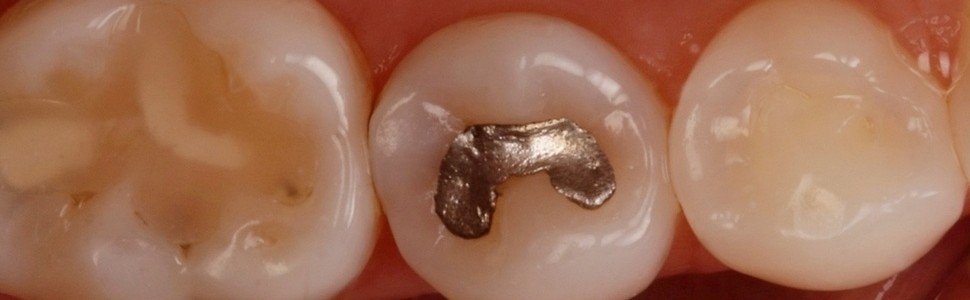

Po analizie zdjęć rentgenowskich pora na ocenę wizualną jamy ustnej pacjentki (ryc. 3).

Ryc. 3. Obraz kliniczny zęba 45.

W zębie 45 znajduje się wypełnienie amalgamatowe I klasy – nie jest ono może idealne, ale wokół nie widać znaczących nieszczelności. Dystalna listewka szkliwna jest trochę ciemniejsza, ale czy nie wynika to z przebarwień związanych z korozją amalgamatu? Po obejrzeniu zdjęcia skrzydłowo-zgryzowego przyglądamy się powierzchniom stycznym tego zęba – niespecjalnie można stwierdzić, czy są tam ubytki. Co dalej? Przystąpić do opracowania czy obserwować? (4).